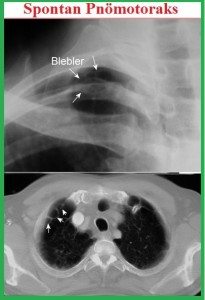

PA akciğer grafisi (ayakta): visseral plevra sınırı görülür. PA normal ama şüphe varsa lateral veya lateral dekubit grafiler çekilebilir. Ekspirium grafisi çok az katkı sağlar. Mediastinal şift; gençlerde minimal pnömotoraksta bile olabilir.

Tansiyon pnömotoraks: Klinik bir durumdur. Takipne, taşikardi, hipotansiyon, ajitasyon vardır klinikte. Hemitoraks geniş, solunuma az katılır, trakea devie, hipertimpanik ses, KTA yer değiştirmiş. Her tür pnömotoraksta oluşabilir. Mekanizma; plevral aralıkta hava birikimi >> ekspirasyonda dışa çıkamaz (tek yönlü valv mekanizması) >> basınç artar ve pozitifleşir >> AC kollapsı, mediastinal ve venöz yapılara bası oluşur >> mediastinal şift >> venöz dönüş azalır >> kardiak dolum ve output azalır >> hipoksemi, şok gelişir.